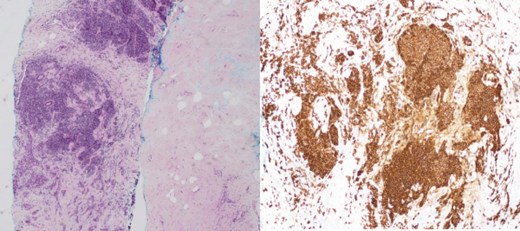

(Left) Breast core biopsy showing neoplastic lymphoproliferation around benign duct (H&E stain, 20 times magnification); (Middle) Breast core biopsy with immunohistochemical staining showing atypical lymphoid cells positive for CD20 stains; (Right) lymph node core biopsy showing distorted architecture by an infiltrate of small lymphocytes involving entire node (H&E stain, 20 times magnification).

Patient B, aged 72, was healthy and presented with left breast pain and a breast lump for 5 months. A 15 mm left breast lump was palpable. Imaging confirmed this finding and revealed bilateral axillary lymphadenopathy (Figs 4 and 5). Core biopsies of the left breast nodule and bilateral axillary nodes were diagnostic of chronic B cell lymphocytic lymphoma (Fig. 6). Positron emission tomography (PET) scan demonstrated disseminated lymphadenopathy involving cervical, mediastinum, and intra-abdominal lymph nodes. As the disease was indolent and she was asymptomatic, she was conservatively managed with active surveillance. Her breast discomfort resolved with analgesia. Follow-up imaging demonstrated stable lymphadenopathy.